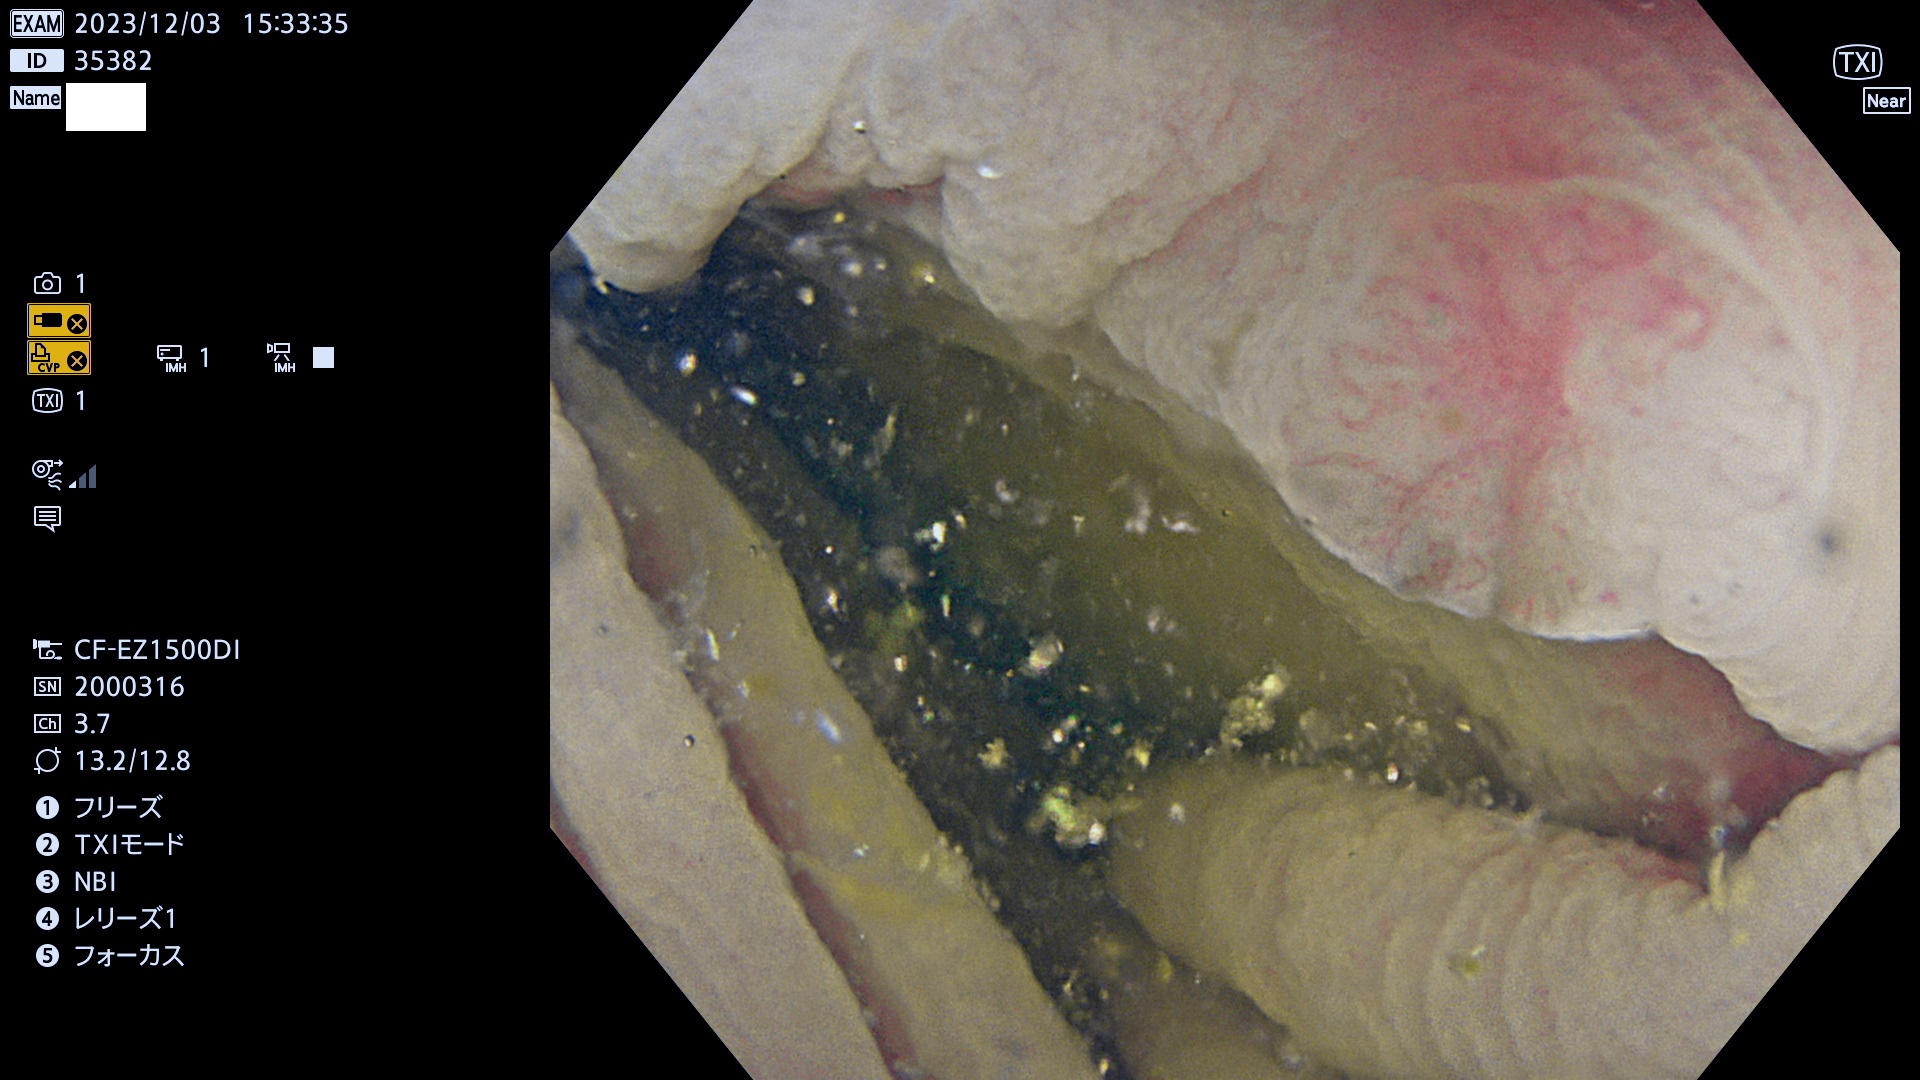

表面型腺腫(Flat Adenoma)の中で、完全に平坦な物をUb、陥凹している物をUcと呼びます。平坦隆起型(Ua)よりも、発見が難しく危険な病変です。このタイプは「内視鏡後・大腸癌の重要犯人」であり、この発見率は「腺腫発見率」よりも、重要な意味があります。

毎週の検査(木・金・土・日)に発見されたUb、Uc型・腺腫を、その週の日曜の夜にUPし1週間、提示します。

抽出の対象期間 2023年11月30日(木)〜12月4(月)の5日間(60件の検査)6件